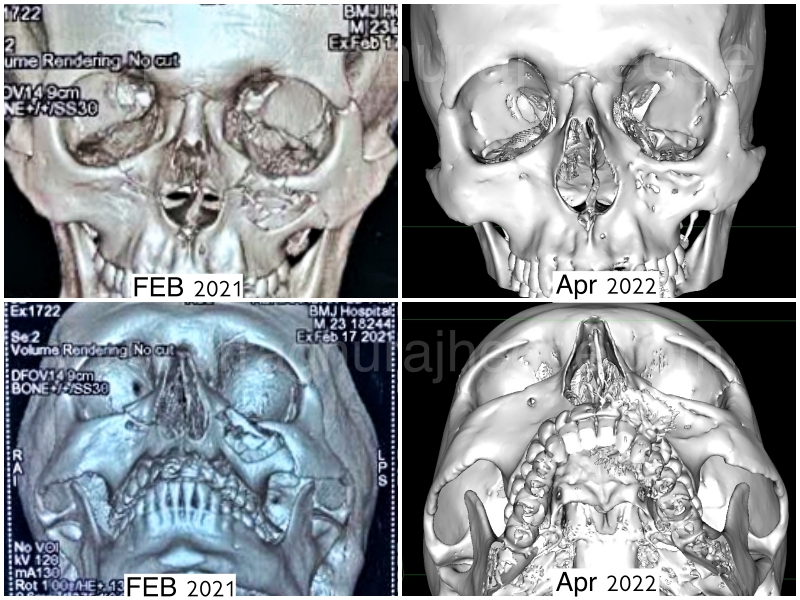

This young man suffered from a Road traffic accident about a year back before he come to see us. He had a left orbital floor fracture with bilateral inferior orbital rim fracture at the time of injury. He refused surgery at the time. Below you can see the old and new 3D reconstruction CT scans dated more than a year apart.

However, slowly he started developing Left eye enophthalmos (eye sinking into eye socket), left orbital deformity compared to right eye. In addition, he had restriction in movement for upgaze and diplopia (double vision) in certain gazes. He was advised a PSI for correction of this late deformity.

His post operative CT scan shows perfect correction of his Floor fracture and zygoma augmentation.